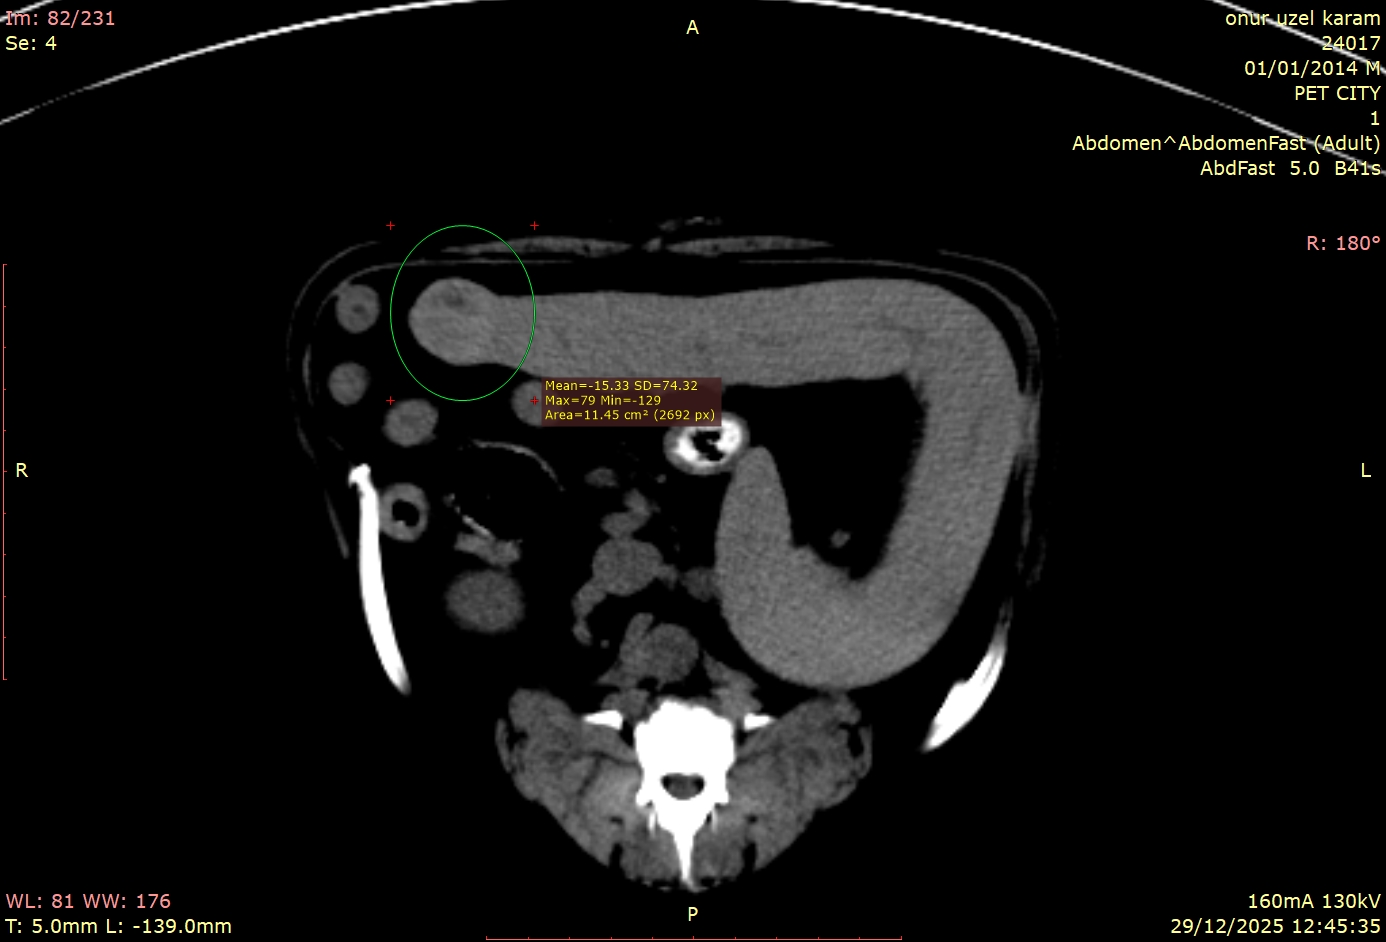

Kliniğimize prostat büyümesi şüphesiyle gelen sevimli dostumuzun hikayesi, doğru tanı araçlarının ne kadar hayati olduğunu bir kez daha kanıtladı. Rutin muayeneler ve klinik belirtiler bize bir yön gösterse de, vücudun içinde tam olarak neler olup bittiğini anlamak için bazen daha derinlemesine bir bakış gerekir. Bu vakamızda, teşhis için Bilgisayarlı Tomografi (BT) çekimine karar verdik. Ancak sonuçlar bize sadece prostatı değil, çok daha fazlasını anlattı.

Geleneksel görüntüleme yöntemlerinin aksine, tomografi bize vücudu katman katman, üç boyutlu bir hassasiyetle inceleme şansı verir. Bu teknoloji sayesinde, hekimlerimiz yalnızca şikâyet konusu olan bölgeyi (bu vakada prostatı) değil, o bölgeyle komşu olan tüm organları, doku yapılarını ve potansiyel riskleri tek bir taramada, en ince ayrıntısına kadar değerlendirebilir.

Hastamızın tomografi görüntülerini incelediğimizde, bizi şaşırtan ve tedavi planımızı kökten etkileyen detaylarla karşılaştık:

Bu vakadaki en kritik nokta, dalaktaki kitlenin tamamen "sessiz" olmasıydı. Hasta sahibinin fark edebileceği hiçbir semptom yoktu. Eğer sadece prostata odaklanıp ileri görüntüleme tekniklerini kullanmasaydık, dalaktaki bu lezyon gözden kaçabilirdi.

Tomografi çekilmemiş olsaydı, bu kitle belki de çok daha ileri bir evrede, tedavi şansının azaldığı bir dönemde karşımıza çıkacaktı. Bu vaka, tomografinin yalnızca mevcut problemi çözmekle kalmayıp, henüz belirti vermeyen gizli tehlikeleri de erken dönemde yakalama gücünü net bir şekilde göstermektedir.